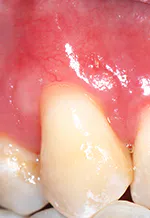

Secondly, gently retract the patient's lip or cheek to gain access, place the periodontal probe on the outside of the tissue, and measure from the gingival margin to the mucogingival junction, and record (see Figure 3).

Thirdly, measure the clinical probing depth (pocket depth to the sulcus) (see Figure 4). To calculate the attached gingiva, subtract the probing depth from the outside measurement of the gingiva for the total width of of attached gingiva. Record the width of the attached gingiva and identify any teeth that need tissue regeneration, such as root coverage surgery (see Miller classification I-III, Table 1).